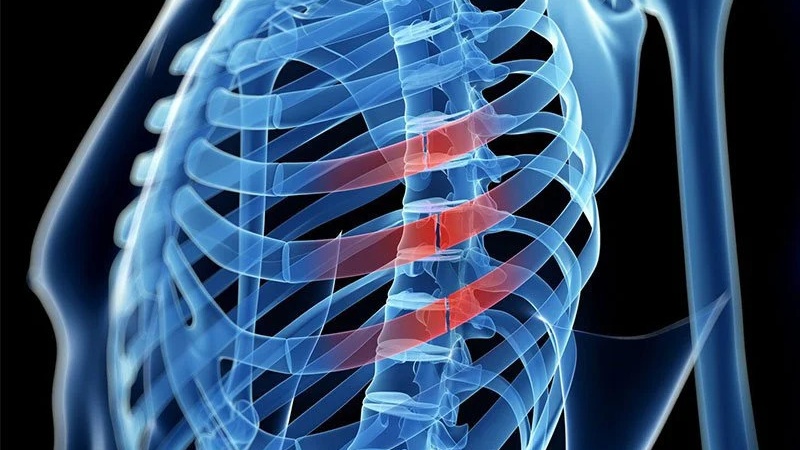

Gãy xương sườn số 5 6 7 sẽ xảy ra khi các xương sườn tương ứng trong lồng ngực bị gãy hoặc nứt.

Xương sườn số 5, 6, 7 là những xương sườn ở phía trên của lồng ngực, gần với phần dưới của xương ức. Khi có chấn thương đủ mạnh, có thể là va chạm hoặc chấn thương lồng ngực, các xương sườn này có thể bị gãy, khiến người bị cảm thấy đau đớn và khó chịu.

Gãy nhiều xương sườn có thể dẫn đến nguy cơ tổn thương các cơ quan nằm bên trong khu vực xương sườn, bao gồm tràn khí màng phổi, tràn máu màng phổi, dập phổi, thủng cơ hoành, lách, gan và các cơ quan khác.